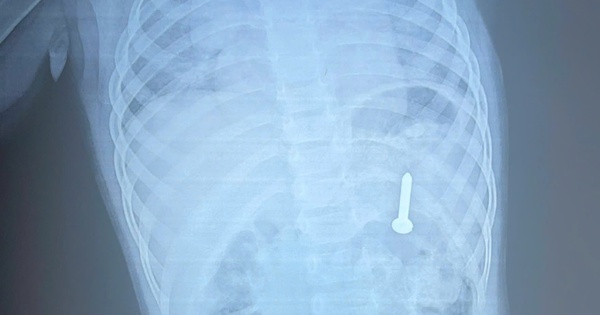

Dị vật sắc nhọn nằm trong dạ dày bệnh nhi 21 tháng tuổi

(NLĐO) - Các bác sĩ đã lấy thành công dị vật sắc nhọn, dài 2,5 cm ra khỏi dạ dày bệnh nhi 21 tháng tuổi